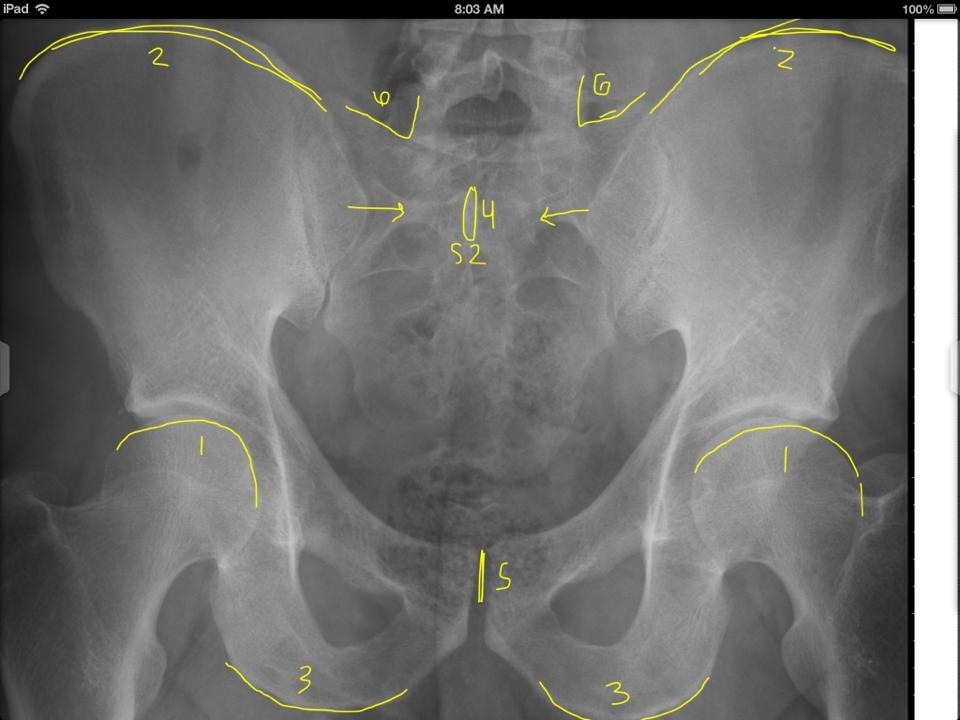

1

Q

A

Superior aspect of femur heads

2

Superior aspects of iliac crest

3

Inferior aspect of ischial tuberosities

4

S2 tubercle

5

Pubic symphysis

6

Sacral Grooves